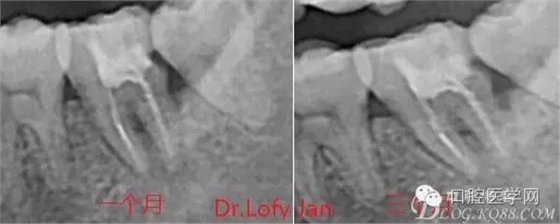

根管治療術(shù)是牙體牙髓疾病治療中最復雜和最關(guān)鍵的治療項目。根管充填材料抵達根尖、并能嚴密堵塞根尖孔,是確保根管治療效果的關(guān)鍵指標。為了保證根管充填到位,醫(yī)生需要在術(shù)前照牙片以了解牙根根管的數(shù)量、彎曲程度和長度,在術(shù)中有時需要插針照牙片來精確測量根管長度,術(shù)后必須照牙片以確定是否根管充填到位,如果欠填或超填,就需要重新充填、重新照牙片確認,直到根管充填到位。所以,在患者接受根管治療時有時會反復照牙片。

病例分析:曲面斷層片在x線輔助診斷與檢查中目前大多數(shù)文獻和著作都建議只能作為初診拍片檢查手段,不能作為終末疾病的確診與手術(shù)療效的評價指標,臨床大部分中小型門診都因為設備不齊全導致信息偏差很大。